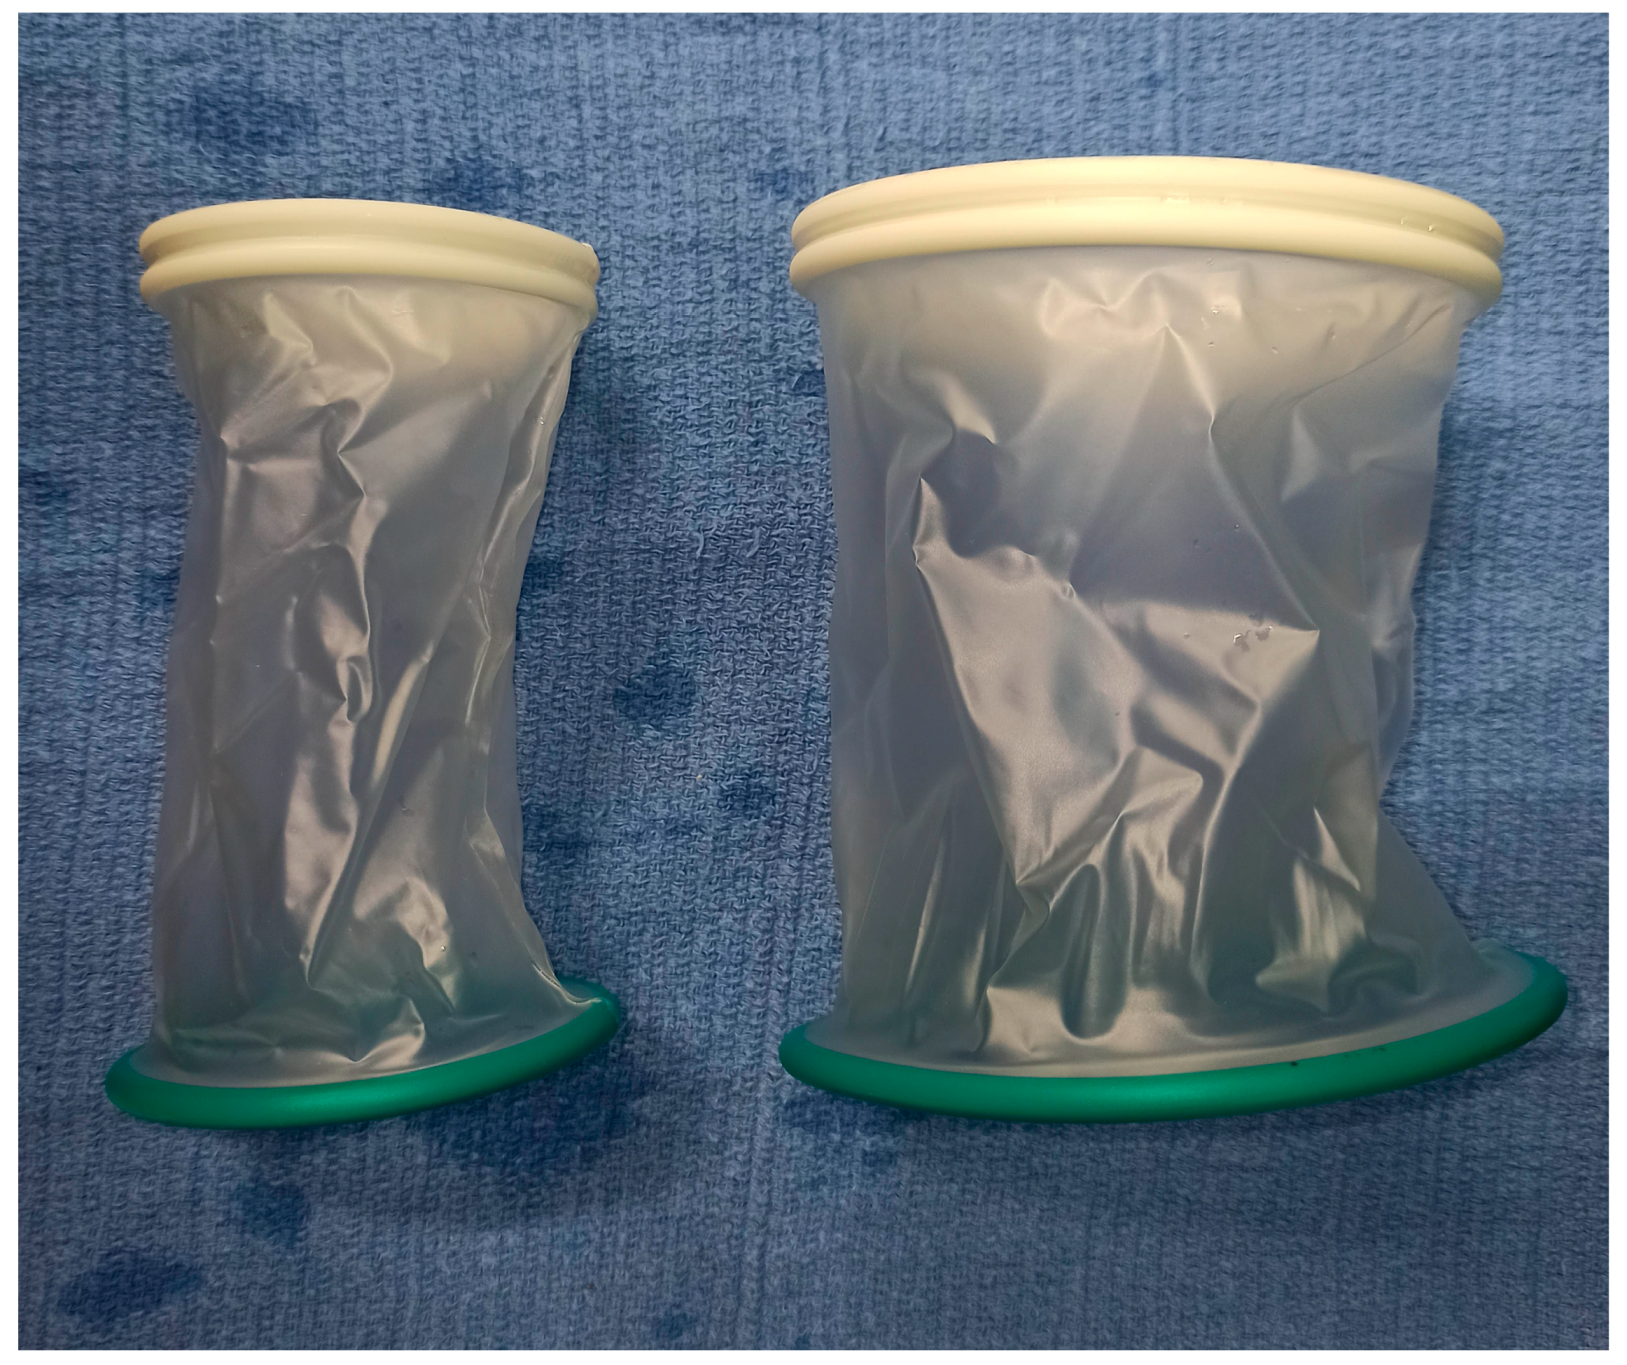

2. Materials and Methods

2.2. Surgery